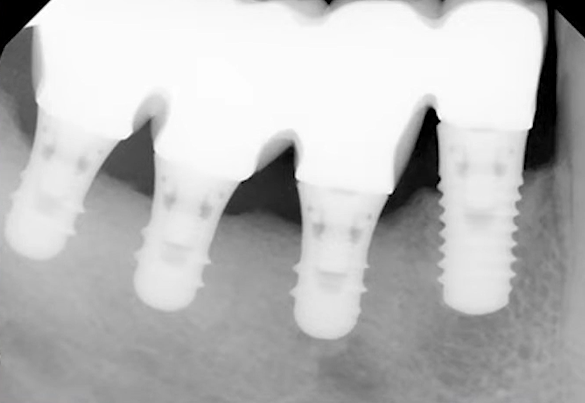

A large 6 mm diameter, 6 mm long implant with a standard thread profile was used. A standard profile means threads are sharper at the apex and become smoother toward the neck.

The available bone height was 7 mm to the floor of the maxillary sinus (see the illustration below).

The implant was placed subcrestally, 1 mm below the marginal bone level. The implant apex was positioned almost at the maxillary sinus floor, as seen in the upper left slide.

Everything seemed fine: The implant was stable. However, a 12-month follow-up showed slight bone resorption, and the implant neck was exposed by about 1 mm.

Considering that the implant was initially recessed by 1 mm, the total loss is 2 mm. If the implant hadn’t been placed subcrestally, no more than 4 mm would have remained in contact with the bone, and now it’s 5 mm, which is still low, but not critically so.